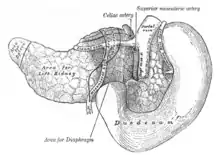

Sections of the small intestine The celiac artery and its branches; the stomach has been raised and the peritoneum removed

The celiac artery and its branches; the stomach has been raised and the peritoneum removed Superior and inferior duodenal fossæ

Duodenojejunal fossa The pancreas and duodenum from behind

The pancreas and duodenum from behind Transverse section through the middle of the first lumbar vertebra, showing the relations of the pancreas